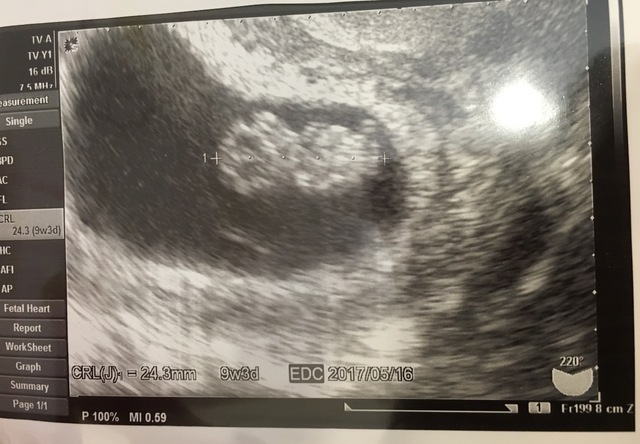

9週3日(9w3d・女の子)|あづママ さん(32歳)

エコー写真撮影時のエピソード:

2回目の検診で胎芽から胎児らしい身体つきになって初めてのエコーでした。

手足をバタバタさせてエコーからここにいるよ~!とアピールしているようで、担当医とナースと元気に動いている様子をみて和みました。 動画を取り損ねてしまったのが心残りですがこのエコーを見る度に思い出します。

生まれたあとも手足は元気すぎるくらい毎日バタバタさせて掛物をすぐにはいでしまっています。